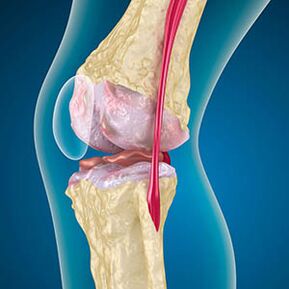

Με την αρθρέωση, ο χόνδρος που καλύπτει τις άκρες των οστών είναι τριβή ή εντελώς απουσιάζει. Ο κατεστραμμένος ιστός δεν αποτελεί πηγή πόνου, επειδή δεν έχει υποδοχείς. Η φλεγμονή στις κοντινές δομές προκαλεί χαρακτηριστικά συμπτώματα.

Το σώμα συνεχίζει την αναγέννηση των κατεστραμμένων ιστών, αλλά ο χόνδρος αυξάνεται άνισα. Ως αποτέλεσμα, σχηματίζονται ανωμαλίες που τραυματίζουν άλλα στοιχεία της άρθρωσης. Η φύση των οστεοφυτών εξηγείται από την αντιστάθμιση για τον ομαλό χόνδρο της άρθρωσης. Μια άλλη έκδοση δείχνει ότι η ανάπτυξη των "Spurs" Συσχετίζεται με μια προσπάθεια σταθεροποίησης της άρθρωσης μεσαία ή πλευρική λόγω της αποδυνάμωσης των μυών.

Η διόγκωση προκαλείται από τραυματισμό σε μαλακούς ιστούς, φλεγμονή των τενόντων και της τσάντας άρθρωσης. Η εμφάνιση θερμότητας στο γόνατο, οίδημα δείχνει τη συσσώρευση φλεγμονώδους εξόδων -Η αρθρίωση συχνά συνοδεύεται από μπιφίτιδα, αρθρίτες, τενοντίτιδα.